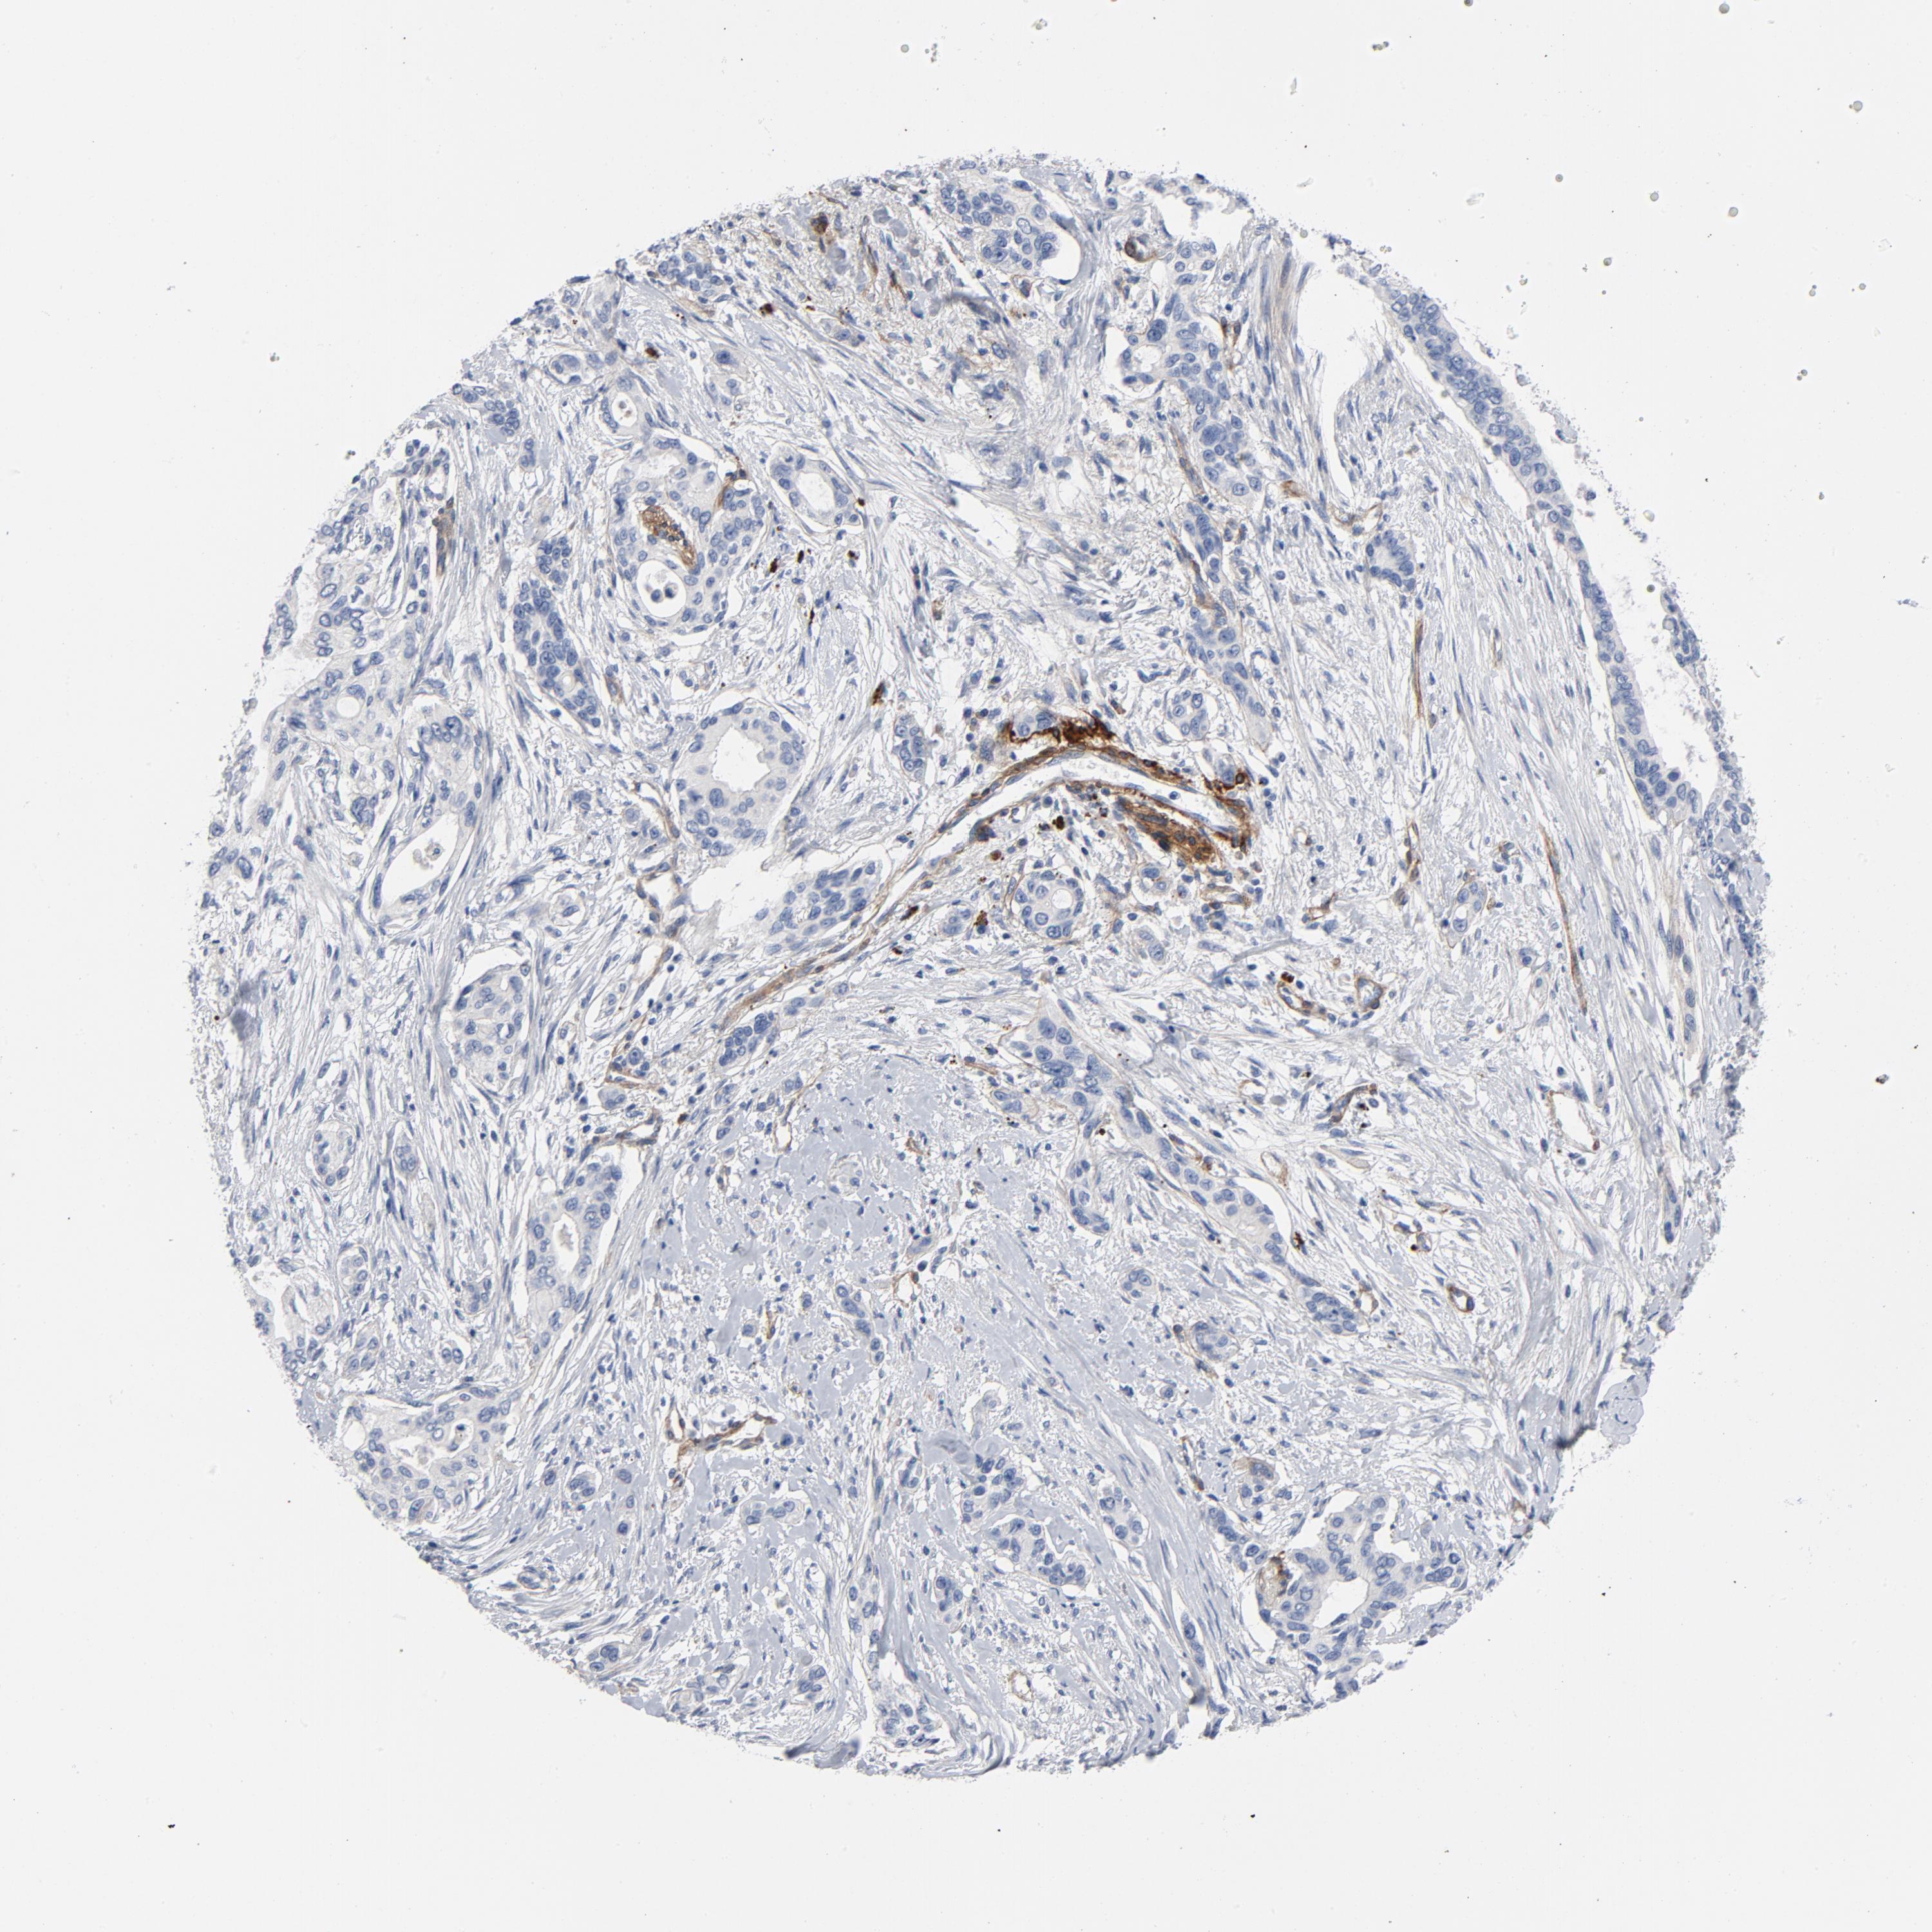

PANCREATIC CANCER - Protein expressioni

A mouse-over function shows sample information and annotation data. Click on an image to view it in a full screen mode. Samples can be filtered based on level of antibody staining by selecting one or several of the following categories: high, medium, low and not detected. The assay and annotation is described here.

Note that samples used for immunohistochemistry by the Human Protein Atlas do not correspond to samples in the TCGA dataset.

Antibody stainingi

Antibody staining in the annotated cell types in the current human tissue is reported as not detected, low, medium, or high, based on conventional immunohistochemistry profiling in selected tissues. This score is based on the combination of the staining intensity and fraction of stained cells.

Each image is clickable and will lead to virtual microscopy that enables deeper exploration of all samples and also displays staining intensity scores, fraction scores and subcellular localization as well as patient and tissue information for each sample.

Antibody HPA001908

Antibody HPA001909

Antibody CAB004486

Antibody CAB078163

Adenocarcinoma, NOS

Adenocarcinoma, metastatic, NOS